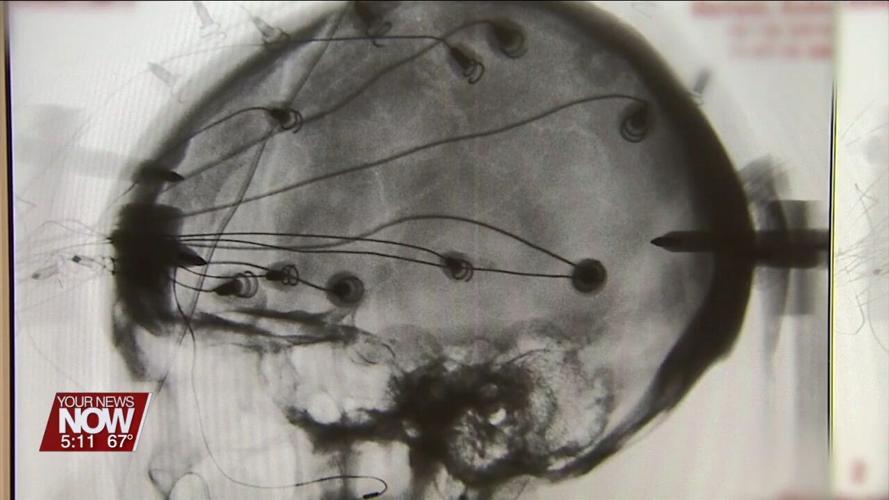

Phase 1 of the trial involved 12 stroke patients suffering from moderate-to-severe muscle weakness on one side of the body, each had electrodes implanted into part of the brain. The electrodes were used to deliver electric pulses to help regain control of movements. Then the participants first underwent physical therapy with the deep brain stimulation device turned off for several weeks and then turned on for four-to-eight months. The most significant improvements were noted with deep brain stimulation turned on, and nine out of 12 people in the trial improved motor impairment and function.